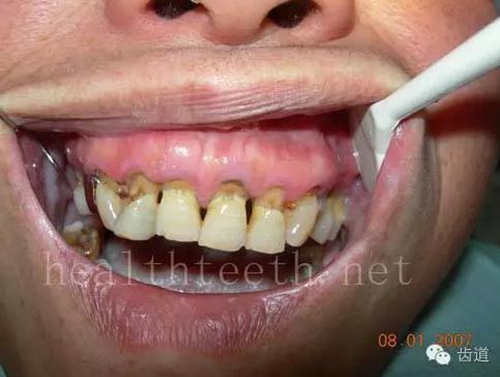

二、牙周組織病

牙周大量牙石堆積

13.jpg